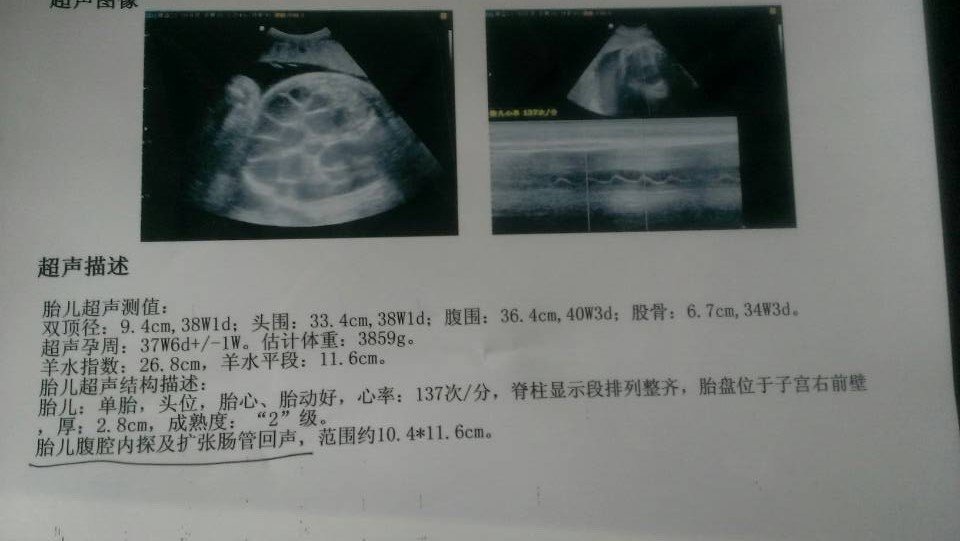

急急!!!!!胎儿腹腔内探及扩张肠管回声 38周了B超检查胎儿腹腔内探及扩张肠管回声,担心担心 在线等 点击展开 匿名用户 2015-01-20 17:02 为您推荐: 其他回答 胎儿腹腔内探及扩张肠管回声 ,不排除是肠道梗阻和肛门闭锁引起的,最好定期复查肠管的扩张程度。 金牛李世峰 2015-01-22 09:32 相关问题 38周,B超检查胎儿腹腔内探及扩张肠管回声,肠管扩张 什么情况?急急 34周于胎儿腹腔内探及局部扩张肠管回声 我女儿4岁腹腔可探及大量扩张之肠管回声